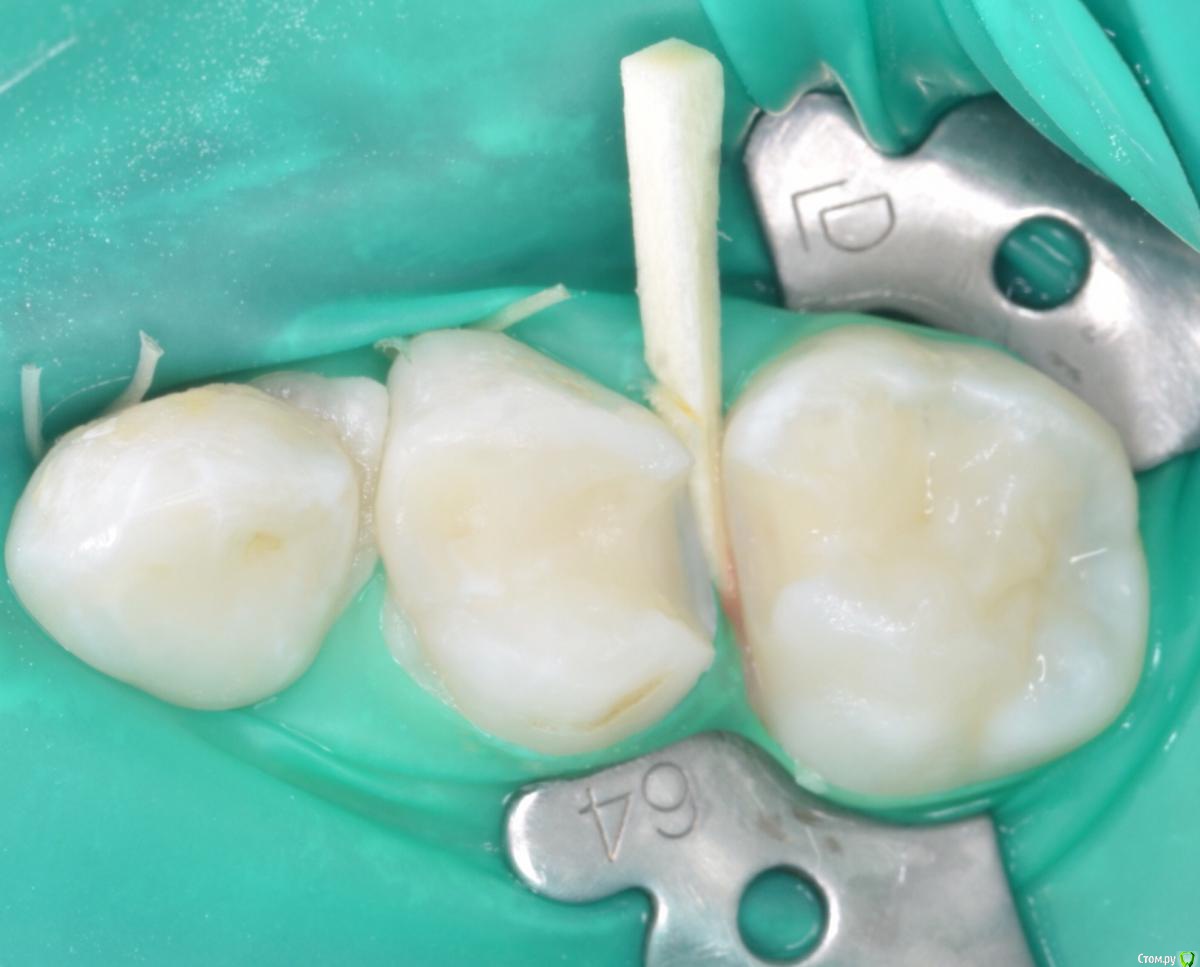

CRAZYDUCK Опубликовано 24 мая, 2018 Автор Поделиться Опубликовано 24 мая, 2018 В этом клиническом случае хочу обратить внимание коллег на покрытие 8.5 зуба коронкой ( что необычного видите ?). И на использование флосса, чтобы заправить платок дистально за 4.6 . 4.6 начальный кариес , но зуб дистально ещё был прикрыт десной ( фото до лечения не делала без коффердама). Раньше во время работы в эту дистальную зону «трамбовала» Фумку . Следила , чтобы не подтекало . Но !!!!Очень удобно эту десну заправлять флоссом - ничего не течёт 1 Ссылка на комментарий

CRAZYDUCK Опубликовано 24 мая, 2018 Автор Поделиться Опубликовано 24 мая, 2018 8.5 ранее лечен методом витальной ампутации( 1,5 года назад ), но реставрация обширная . Не выдерживает жевательную нагрузку . 2 Ссылка на комментарий

CRAZYDUCK Опубликовано 24 мая, 2018 Автор Поделиться Опубликовано 24 мая, 2018 Я всегда перед лечением очищаю зубы кавопрофифлекс ( все зубы , которые попали в зону изоляции ), поэтому изначально планировали только покрыть 8.5 коронкой . Из-за этого изоляция такая ( никакая), но после чистки 4.6 стало ясно , что планы немного меняются . Ссылка на комментарий

crown Опубликовано 24 мая, 2018 Поделиться Опубликовано 24 мая, 2018 (изменено) В этом клиническом случае хочу обратить внимание коллег на покрытие 8.5 зуба коронкой ( что необычного видите ? Коронка от другого зуба? Изменено 24 мая, 2018 пользователем crown Ссылка на комментарий

CRAZYDUCK Опубликовано 25 мая, 2018 Автор Поделиться Опубликовано 25 мая, 2018 (изменено) Коронка от другого зуба? да , 6.5 на 8.5 , можно заменять в случае необходимости . Изменено 25 мая, 2018 пользователем CRAZYDUCK Ссылка на комментарий